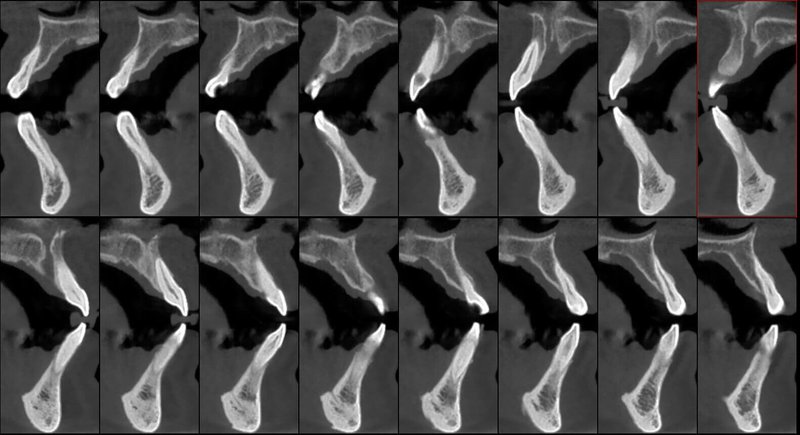

- Мощная диагностика

- Технология HR от Newtom

КОМПЛЕКСНЫЙ ГИБРИДНЫЙ КЛКТ ДЛЯ 2D/3D ВИЗУАЛИЗАЦИИ. ИЗОБРАЖЕНИЯ В ВЫСОКОМ РАЗРЕШЕНИИ С ЗАХВАТОМ МЕЛЬЧАЙШИХ ДЕТАЛЕЙ

GIANO HR – универсальное обновляемое устройство от NewTom для всех задач, связанных с радиографией. Благодаря полному диапазону опций 2D и 3D исследования для стоматологии оно предлагает множество особых трехмерных обследований для челюстно-лицевой хирургии, оториноларингологии и осмотра шейного отдела позвоночника. Визуализация только наивысшего качества с технологиями и опытом NewTom

NNT – программное обеспечение NewTom, предоставляющее несколько специальных режимов применения для имплантологии, эндодонтии, пародонтологии, челюстно-лицевой хирургии и радиографии. Это мощное технологически новейшее устройство, разработанное, чтобы снимать и обрабатывать изображения в несколько простых шагов для получения информации, необходимой для конкретного подробного диагноза пациенту. Продвинутое устройство, дающее врачу специальные инструменты для измерения анатомической области (расстояния и углы), нахождения нижнего альвеолярного нерва и замера объема верхних дыхательных путей.

NewTom GiANO HR новейшая модель была официально представлена на международном конгрессе радиологов ECR 2018 в марте в Вене. Благодаря обновленным системам механики и запатентованным механизмам работы аппарат отличается от своих сверстников Высочайшим качеством получаемых изображений, как 2D, так и 3D. Лучшее качество снимков и мы отвечаем за это! Этот аппарат заменит три аппарата! Панорамный аппарат, цефалометрическая приставка и конусно-лучевая компьютерная томография интегрированы в единую платформу. В комплекте детектор для выполнения 3D исследований с захватом области 13х16 см, Сьемный 2D CMOS детектор для выполнения панорамных исследований, и ТРГ.